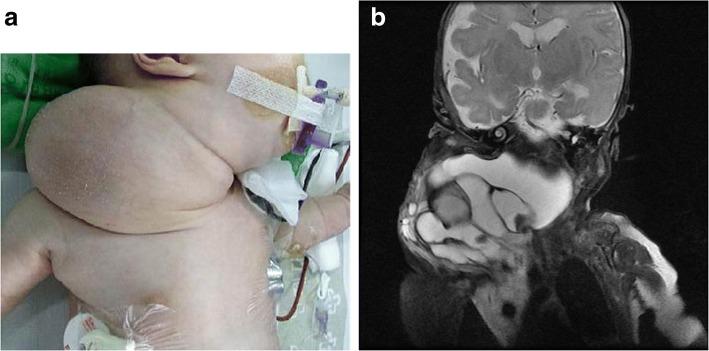

Lymphatic malformations are histologically benign vascular structures that vary in anatomic lesion and size. Extensive head and neck lymphatic malformations may be life-threatening. In the present study, we described three difficult-to-treat infants with giant cervico-mediastinal lymphatic malformations accompanied by severe respiratory distress.

Case 1. A Korean girl born at a gestational age of 37 weeks and weighing 2920 g had a large cervical mass compressing the trachea. Despite initial OK-432 sclerotherapy, the mass extended over the contralateral retropharyngeal space and mediastinum. Although the cervical mass was completely excised, our patient was not weaned off the ventilator. The mediastinal lymphatic malformation was excised, and our patient underwent continued intensive respiratory care with nasal continuous positive airway pressure for 6 months. She is now 5 years old and doing well without any sequelae. Case 2. A 5-month-old Korean boy showed respiratory difficulty with feeding intolerance after partial excision of a neck lymphatic malformation. We found that the remnant cervical mass had grown into the retropharyngeal space and mediastinum. After a second operation for the cervico-mediastinal mass, he experienced severe respiratory difficulty requiring ventilator care for 6 months. However, he died from central-line fungal sepsis. Case 3. A 30-day-old Korean girl was referred for remnant lymphatic malformation after partial excision. The cervical mass extended to the mediastinum and occupied half of the thoracic cavity, encasing all of the major vessels. After surgical excision, she underwent ventilator care and pleurodesis three times with doxycycline for recurrent pleural effusion. At the age of 26 months, she was weaned off supplementary oxygen and she showed normal development without any sequelae.

淋巴管畸形是组织学上良性的血管结构,其解剖病变和大小各不相同。广泛的头颈部淋巴管畸形可能危及生命。在本研究中,我们描述了三名患有巨大颈纵隔淋巴管畸形并伴有严重呼吸窘迫的难治性婴儿。

病例1。一名孕37周出生、体重2920克的韩国女孩,颈部有一个巨大肿块压迫气管。尽管最初进行了OK-432硬化治疗,但肿块扩展到对侧咽后间隙和纵隔。尽管颈部肿块被完全切除,但我们的患者仍未脱机。纵隔淋巴管畸形被切除,我们的患者接受了持续6个月的鼻持续气道正压通气强化呼吸护理。她现在5岁,情况良好,没有任何后遗症。病例2。一名5个月大的韩国男孩在颈部淋巴管畸形部分切除后出现呼吸困难和喂养不耐受。我们发现残留的颈部肿块已长入咽后间隙和纵隔。在对颈纵隔肿块进行第二次手术后,他出现了严重的呼吸困难,需要呼吸机护理6个月。然而,他死于中心静脉导管相关真菌败血症。病例3。一名30天大的韩国女孩因部分切除后残留淋巴管畸形前来就诊。颈部肿块延伸至纵隔,占据胸腔的一半,包绕所有主要血管。手术切除后,她因复发性胸腔积液接受了三次呼吸机护理和强力霉素胸膜固定术。在26个月大时,她停用了补充氧气,发育正常,没有任何后遗症。